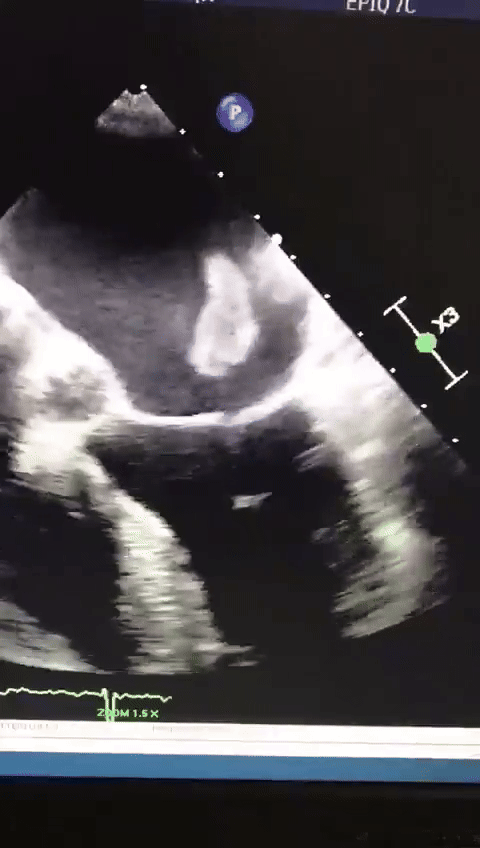

[스크랩] [흥미돋]심장 판막에서 뛰고있는 혈전.gif